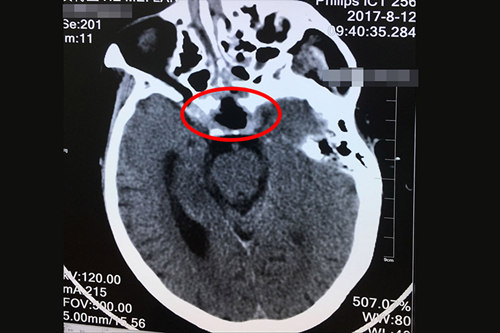

术后CT显示:鞍区垂体大肿瘤切除术后,大脑半球、小脑及脑干形态如常。